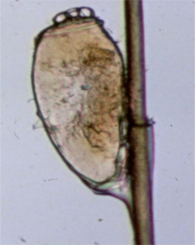

Площица. Заметьте, что площицы могут обхватывать волосы, чтобы вошь могла забираться вверх (для того, чтобы откладывать яйца) и вниз по волосам (чтобы кусать и питаться).

Площицы откладывают и приклеивают яйца к волосам. Эти яйца называются "блохи" и от них очень трудно избавиться. Вам нужно будет увеличительное стекло, чтобы их увидеть.